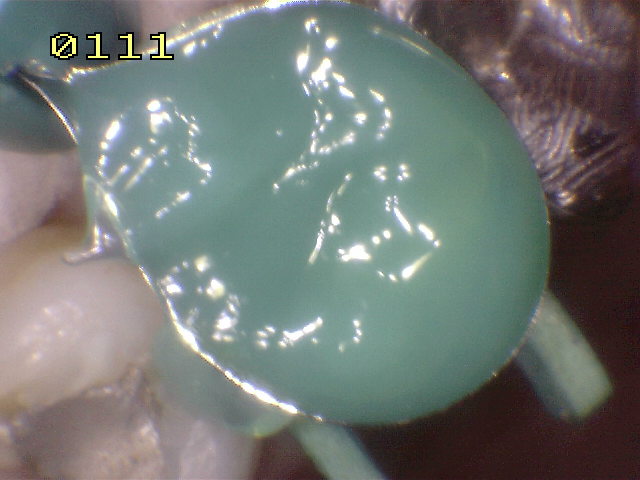

También se baja la cúspide vestibular o de corte , para prevenir una fractura dental.. Se coloca una matriz circular, se acuña y se bruñen los puntos de contacto y por ultimo se graba con acido durante 30 segundos. Se seca por 30 segundos, se aplica el agente de enlace y se activa con luz halógena por 20 segundos. La resina compuesta flow  es aplicada en la caja mesial y distal para fijar la matriz, una vez polimerizada.

Se cubre el esmalte y dentina co una fina capa de resina flow y se polimeriza durante 20 segundos. Se compacta  la resina compuesta  hibrida en capas no mayor de 2 mm. Hasta darle la morfología oclual adecuada.

Reconstrucción terminada.